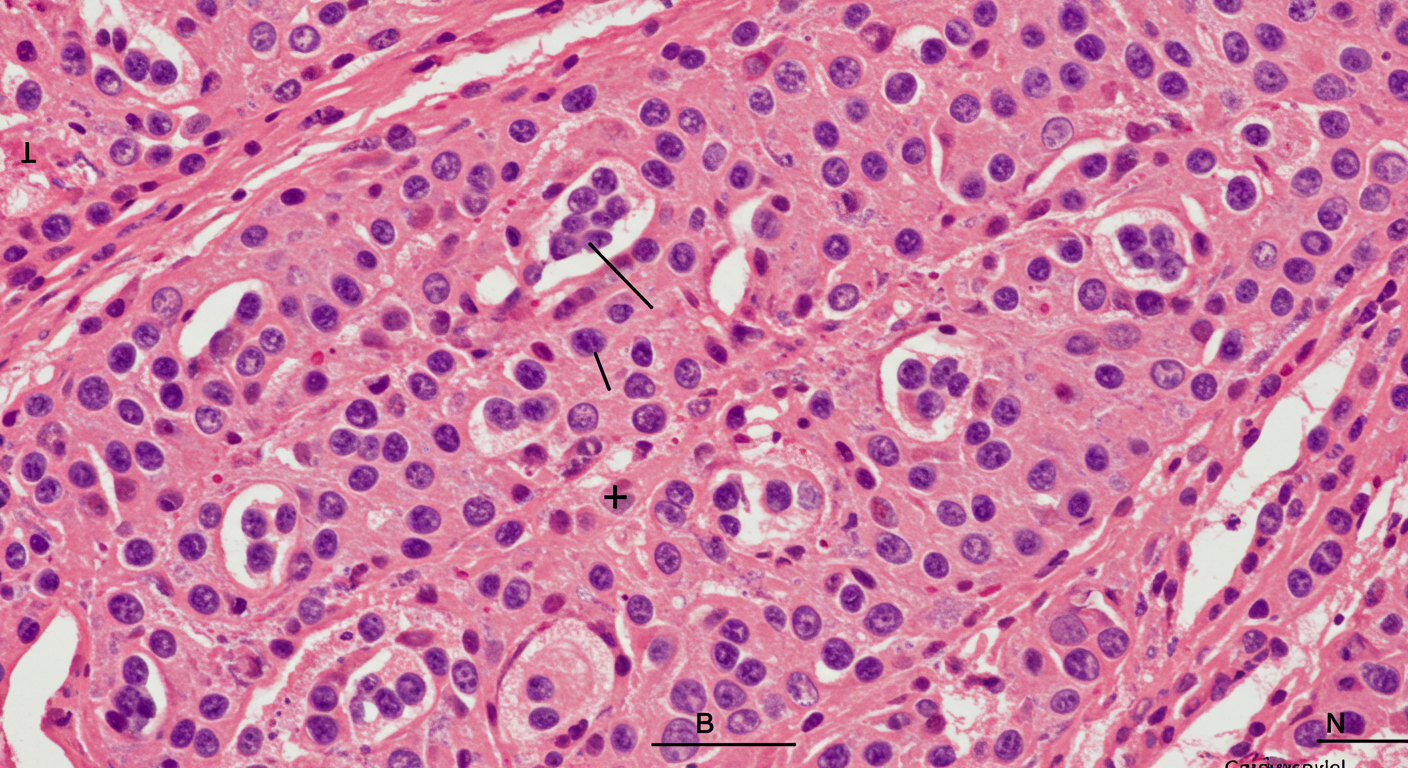

심근세포 비정상 배열(섬유화) → 전기 신호 전달 불규칙